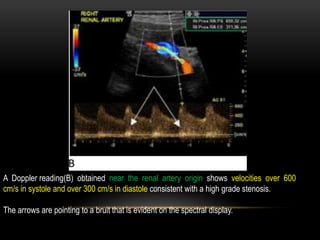

Patient with renal artery stenosis

Image A is a color Doppler image of a stenotic right renal artery origin.

A color bruit is seen in the tissue surrounding the area of the post stenotic turbulence.

The presence of the bruit can help to identify the location of the stenosis and increase

diagnostic confidence.

A Doppler reading(B) obtained near the renal artery origin shows velocities over 600

cm/s in systole and over 300 cm/s in diastole consistent with a high grade stenosis.

The arrows are pointing to a bruit that is evident on the spectral display.